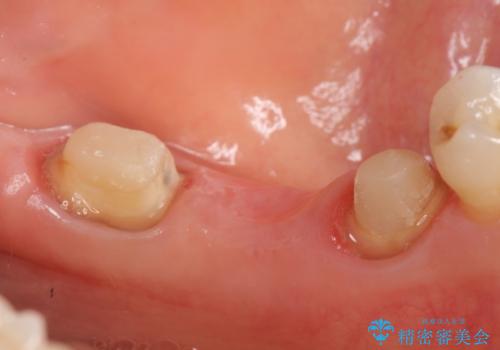

左下7の遠心部は部分的な骨欠損によるポケットが10mmあったため、再生療法による骨の再生を行いました。

再生療法について

再生療法とは歯槽骨の欠損部位を人工骨で補うことにより骨を再生させる手術です。

この手術を行うことで、歯周基本治療では治癒しない歯周病を改善したり、本来ならば抜歯しなければならない歯を保存することができます。